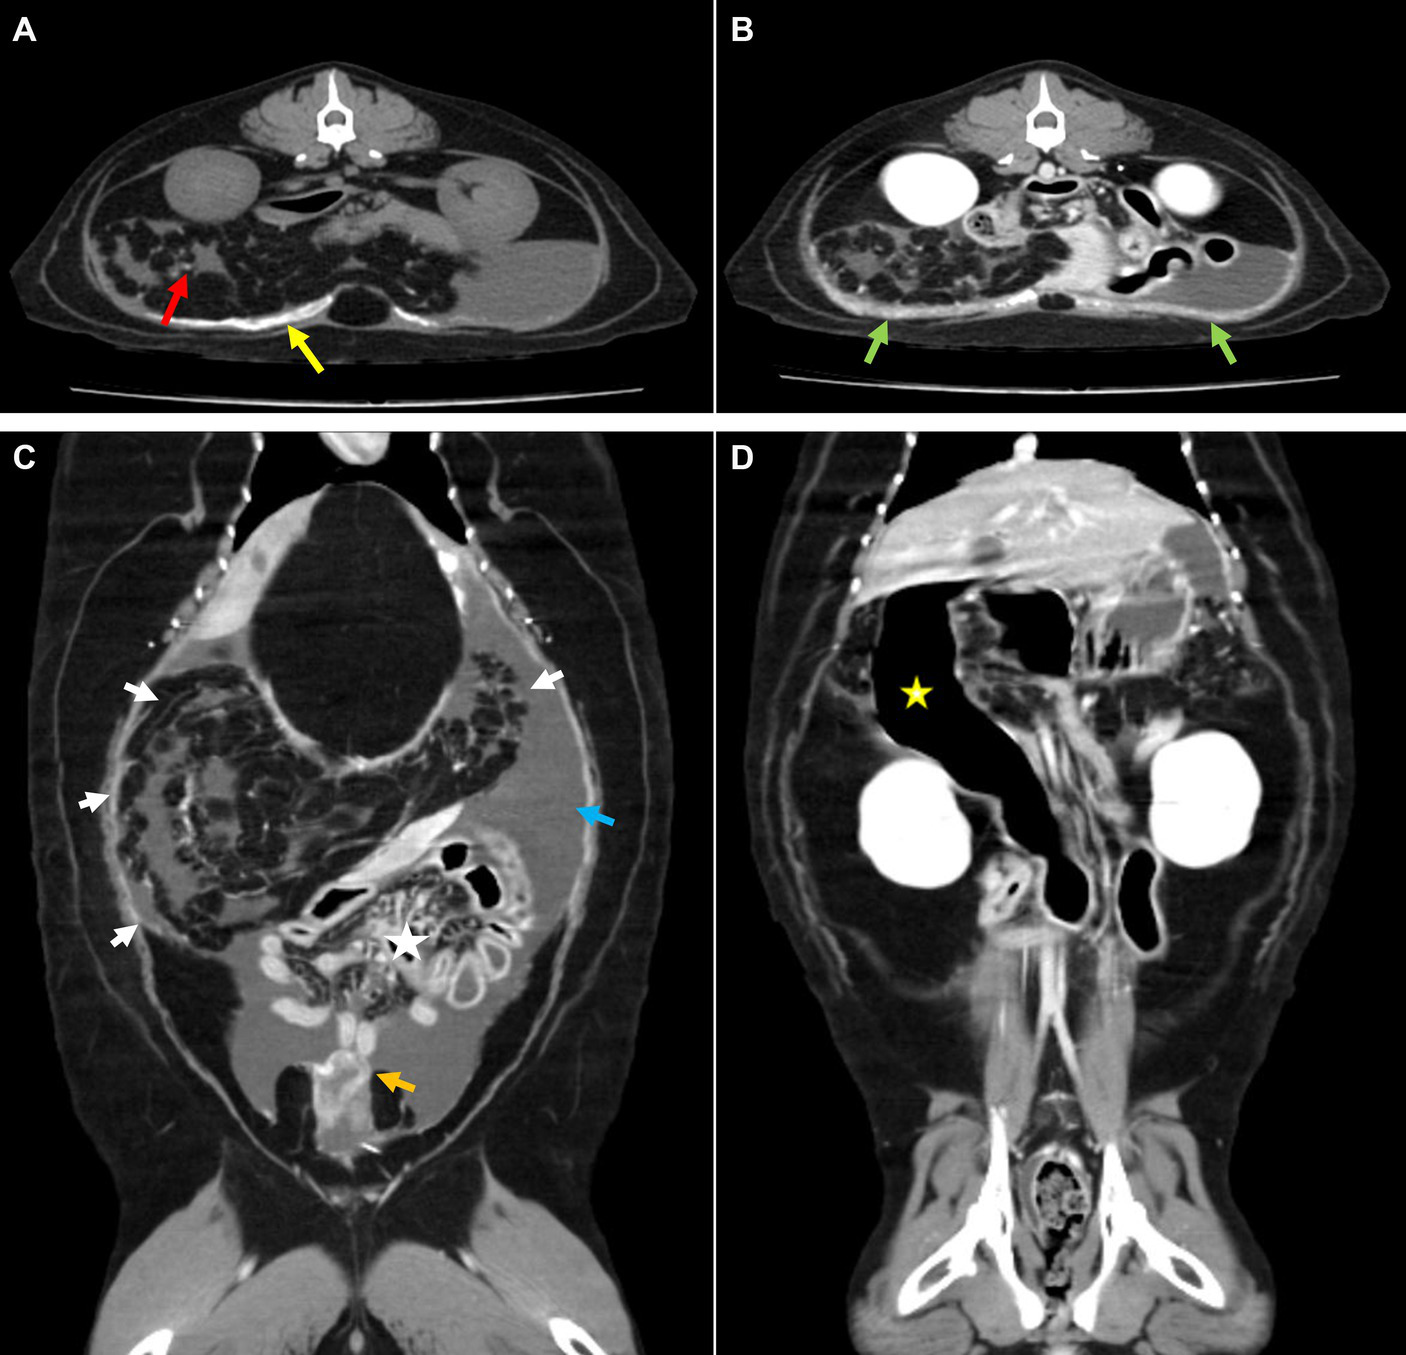

Computed tomography (CT; Brivo CT 385, GE Hangwei Medical System Co., Ltd., Beijing, China) was performed under general anesthesia in sternal recumbency on next day to achieve an accurate diagnosis and for surgical planning (Figure 2). For CT scans, general anesthesia was performed for a total of 1 h, and major vital signs were measured at 5 min intervals. Butorphanol 0.2 mg/kg and midazolam 0.1 mg/kg were used as pre-medication, and induction was performed using propofol 6 mg/kg IV and isoflurane was used for maintenance. Acquisition parameter were as follows: helical mode, 120kVp, exposure 120–200 mAs, 2.5 mm slice thickness, 2.5 mm spacing. Contrast injection was manually performed and images were acquired 35 s following bolus injection. Multi-planar reformatting (MPR) was performed to obtain transverse, sagittal, and dorsal planar images with following parameters; 2 mm slice thickness, 2 mm spacing. Mesenteric and omental fat stranding was observed as multiple linear hyper-attenuations clumped in the right craniolateral abdominal cavity. This resulted in left caudolateral displacement of the stacked bowels and peritoneal effusion. Some small bowels were filled with gas, and the descending duodenum was severely dilated with retained gastric fluid. Strong enhancement was observed in the thickened parietal and visceral peritoneum around the urinary bladder. Extensive calcification was observed in the ventral parietal peritoneum and small calcified foci were observed in the omentum and mesentery. Based on these CT findings, EPS was suspected to have caused the ascites.

Figure 2

Computed tomography. (A) Pre-contrast and (B–D) post-contrast CT images. (A) Broad calcification at the parietal peritoneum (yellow arrow) and small calcified foci at the mesentery (red arrow). (B) Thickened peritoneum showed strong enhancement (green arrow). (C) Gathered omentum and mesentery at the craniolateral abdominal cavity were observed with fat stranding (white arrow), which caused intestinal displacement toward the lower abdomen (asterisk). Surrounding peritoneal effusion (blue arrow) and thickened visceral peritoneum adjacent to the urinary bladder (orange arrow) were also detected. (D) An abnormally dilated descending duodenum with gas was identified (yellow asterisk).